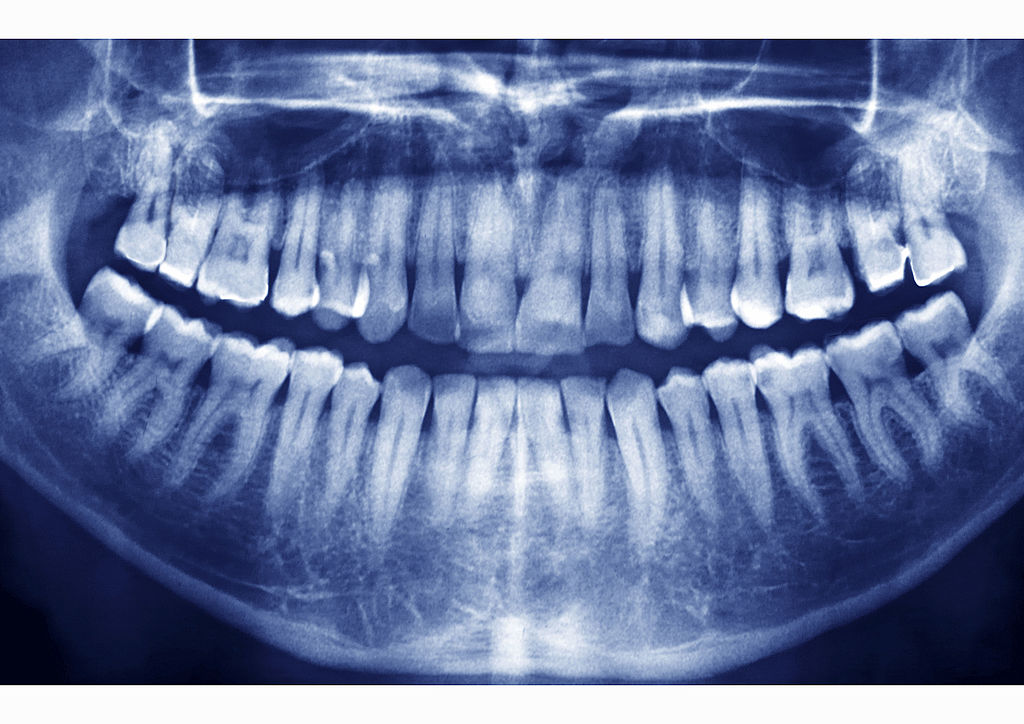

Ретенция – затрудненное прорезывание зуба. Ретинированным может быть любой зуб. Наиболее часто затрудненное прорезывание встречается у нижних зубов «мудрости». Чаще ретинированные зубы обнаруживаются при рентгенологическом исследовании случайно, но иногда они доставляют немало неприятных минут пациентам. Клинически проявляется боль в нижней челюсти соответствующей стороны, которая иррадиирует в ухо, висок, верхнюю челюсть, появляется отек слизистой оболочки, затрудняется глотание и открывание рта.

Ретенция зуба может бывает частичной, неполной, когда зуб прорезался не до конца, но полностью так и не появился. При полной ретенции на рентгене зуб виден, но прорезываться он не собирается, а располагается неправильно и мешает соседним зубам правильно развиваться и расти.

Диагностика ретинированного зуба, скрытого в десне проводится таким образом: рентген, ортопантомограмма, компьютерная томография. Эти методы исследования покажут, есть ли воспалительный процесс, как именно расположены патологически выросшие зубы в челюсти.

Диагностика дистопированного зуба: ортопантомограмма, телерентгенография с целью оценки соответствия друг другу челюстей и коронок зубов.

Диагностика дистопированных (с нарушенным положением) или ретинированных зубов включает прицельную рентгенограмму и панорамный снимок – ортопантомограмму, а также компьютерную томографию. Эти снимки позволяют стоматологу определить, можно ли обойтись без удаления зуба. Определяется положение ретинированного зуба – небное или вестибулярное (как правило, при вестибулярном положении зуб легче вытянуть), проводится диагностика анкилоза, а также врач определяет, можно ли зуб вытянуть ортодонтически, при помощи специальных приспособлений.